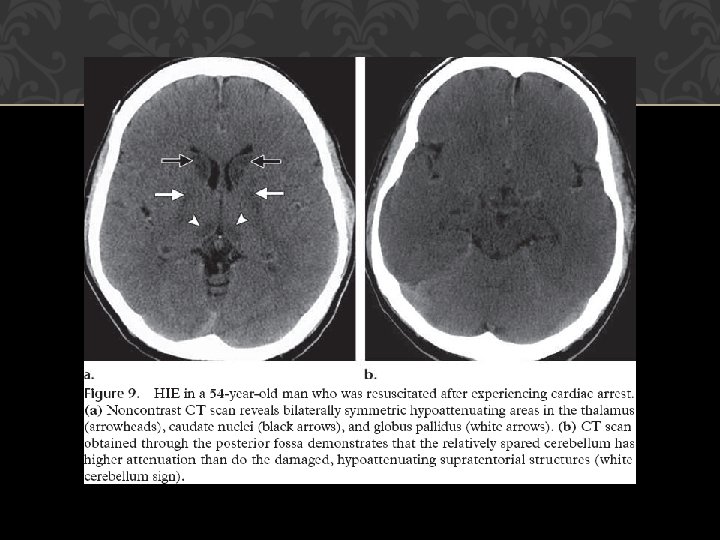

Spanish Hie Multimedia Accidente Cerebrovascular

Signo Del Cerebelo Blanco O Signo Reverso Neurologia Argentina